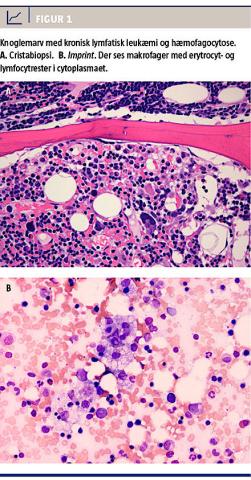

Koagulationsfaktorerne forblev normale under hele forløbet, men der var aftagende nyrefunktion. P-ferritinkoncentrationen var svært forhøjet, 40.300 mikrogram/l (referenceværdi: 12-300 mikrogram/l), hvilket gav mistanke om hæmofagocytosesyndrom. En knoglemarvsundersøgelse viste CLL uden transformering, og der var en infiltrationsgrad på ca. 20% af hæmofagocyterende makrofager i områder af marven (Figur 1). På mistanke om, at hæmofagocytosesyndromet var virusassocieret, blev der herefter påbegyndt behandling med intravenøst administreret